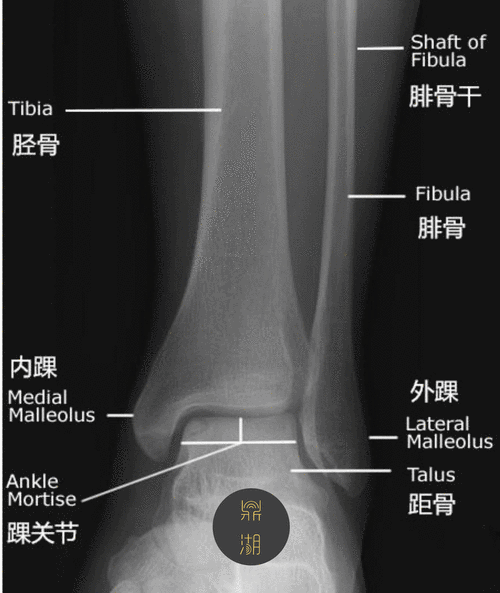

x线解剖 | 踝关节解剖